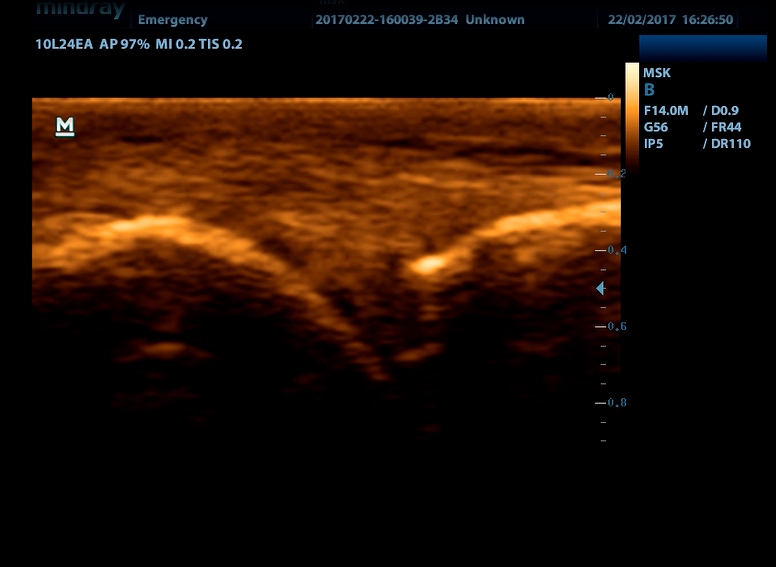

Линейный датчик высокочастотный 10L24EA (8.0/10.0/12.0/14.0/Н10.0/Н12.0 МГц, 24 мм)